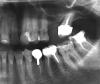

Несмеяна Опубликовано 3 февраля, 2010 Поделиться Опубликовано 3 февраля, 2010 Здравствуйте, уважаемые специалисты. Привожу в порядок рот. И возникли некоторые вопросы: Первый снимок: Как вы оцениваете состояние пломбирования нижней шестерки слева - я собираюсь ставить под нее коронку. Надо ли его перепломбировывать? Пломба там во весь зуб, стенки тонкие. Второй снимок: На верхней шестерке справа хочу поменять коронку (сейчас стоит штампованная и она сместилсь). Можно ли не проходить каналы - зуб резрциненный, не болит. Просто врач говорит проходить надо, но без гарантии, а цена вопроса минимум 15 тыр. Может лучше просто одеть кронку за 7 тыс. без той же гарантии и пусть стоит зубик? А потом когда-нибудь имплант? Скажите, как лучше поступить? И еще вопрос по поводу каналов - 2 сверху - надо перлечивать? Можно ли оставить зуб, наложив винир или лучше убрать под коронку. Какую коронку лучше поставить на передний зуб, чтоб не чернела десна?И еще подскажите, 3 - снизу - нормально залечен, стоит ли его тоже заново лечить? Может еще у меня есть какие-то проблемы, которые заметны по снимку и требуют срочного решения?Заранее благодарна Ссылка на комментарий

Vareнька Опубликовано 3 февраля, 2010 Поделиться Опубликовано 3 февраля, 2010 Здравствуйте, уважаемые специалисты. Привожу в порядок рот. И возникли некоторые вопросы:.... Перед покрытием коронками , рекомендую перелечить корневые каналы во всех указанных Вами зубах. Отсутствие боли еще не указывает на то, что там нет проблемы. Ссылка на комментарий

Андрей Опубликовано 3 февраля, 2010 Поделиться Опубликовано 3 февраля, 2010 Советую перелечить все каналы. Ссылка на комментарий

Русик Романтик Опубликовано 3 февраля, 2010 Поделиться Опубликовано 3 февраля, 2010 Советую перелечить все каналы.и незабудьте подлечить нижнюю восьмерку,судя по снимку она не в отличном сост. Ссылка на комментарий

Dr. Surkin Опубликовано 3 февраля, 2010 Поделиться Опубликовано 3 февраля, 2010 (изменено) и незабудьте подлечить нижнюю восьмерку,судя по снимку она не в отличном сост. Левые восмерки как нижнюю, а равно и верхнюю (наверное семерку) надо удалять. Слева сверху - синус лифт и имплантация. Изменено 3 февраля, 2010 пользователем Dr. Surkin Ссылка на комментарий